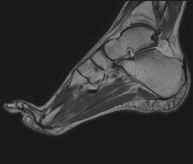

- Ankle MRI

Examination to study the joint and its frequent ligament injuries (sprains) as well as damage to other structures such as cartilage or bone. It is also very useful for diagnosing disorders of the Achilles tendon (tendinitis, ruptures). Duration: approximately 20 minutes. It is a radiation-free procedure.